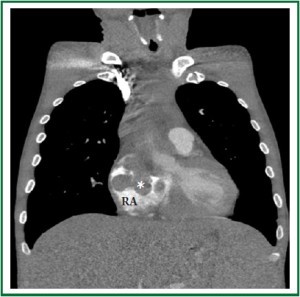

A 46-year-old Caucasian male was admitted to the emergency room with progressive dyspnea, lower limb edema and intermittent fever for 1 month. Past medical history included HIV infection for 20 years, with irregular highly active antiretroviral therapy (HAART) treatment. He had a history of smoking, alcoholism and cocaine addiction. On physical examination, the patient presented with a rapid respiratory rate, blood pressure of 118×68 mmHg and heart rate of 104 bpm. Laboratory data revealed hemoglobin concentration of 6.7 g/dl, white blood cell count of 3.600 /mm3 and platelet count of 22.000 /mm3, with a CD4 count of 49 cels /μl. Computed tomography demonstrated a large, infiltrative, solid mass involving the ascending aorta, pulmonary artery, right ventricle and both atria (Figure 1 and Figure 2) with a lymph node conglomerate in the anterior mediastinum. Transthoracic echocardiography revealed biatrial dilation, mild left ventricular hypokinesia and severe right ventricular impairment. A large echodense mass with irregular borders filled almost completely the left atrium (Figure 3), while another mass was observed inside the right atrium (Figure 4), both attached to the interatrial septum. Increased transvalvular mitral and tricuspid gradients were observed by Doppler study. HAART was started along with intratechal methotrexate, followed by intravenous dexamethasone. Mediastinal biopsy revealed a HHV8-positive PBL. Tumoral cells showed positivity for immunohistochemical markers HHV8, MUM-1, CD138 (focal), CD20 (focal) and Ki67 (high index), whereas CD3 and Epstein-Barr virus (EBV) resulted negative. Bone marrow biopsy showed rare neoplastic cells, compatible with interstitial infiltration by HHV8-positive PBL. Chemotherapy with cyclophosphamide was started. A control echocardiogram after 3 days showed no tumor regression, but significant deterioration of systolic ventricular function. The patient developed hemodynamic instability and worsening of respiratory pattern, requiring ventilatory and hemodynamic support. Despite therapy, the patient died the following day.

Figure 2. Contrast computed tomography (coronal view) showing a large lobulated mass (*) involving the middle mediastinum and extending into the right atrium.